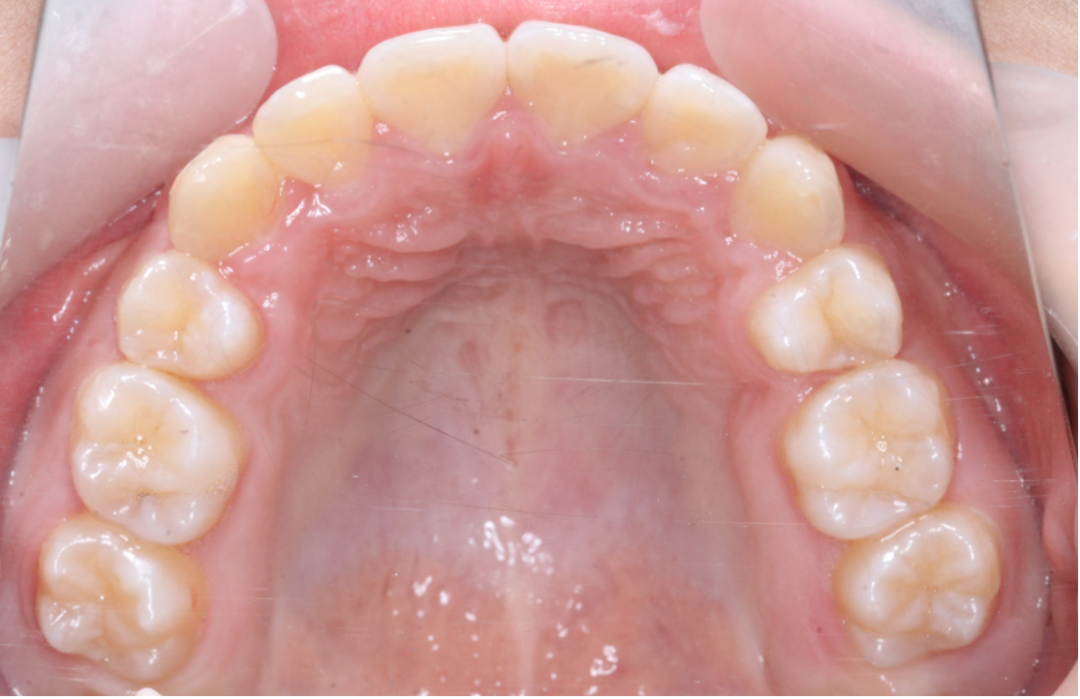

治疗前                        治疗后

无托槽隐形矫治技术

儿童错合畸形早期矫治是阻断影响儿童颌骨、牙齿正常发育的因素,促进颌面部正常发育,降低II期矫正的难度,减少II期矫正的时间,甚至不需要II期矫正。让孩子早期获得自信,绽放灿烂笑容。

术前→术后